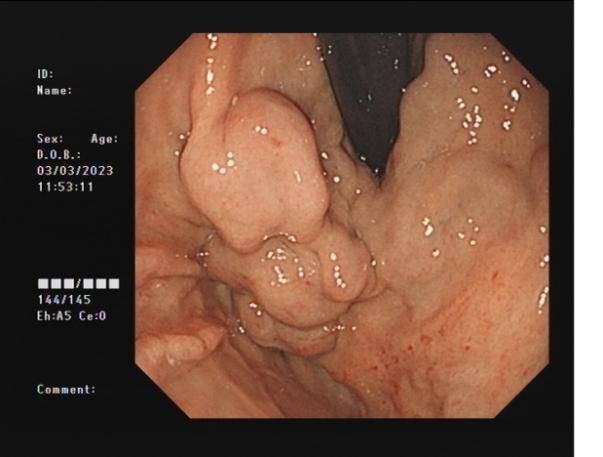

食管靜脈曲張 內鏡下套扎術

食管靜脈曲張套扎術(EVL):治療食管靜脈曲張、胃底靜脈曲張破裂出血、藥物止血無效者;既往有食管靜脈曲張破裂出血史者預防再出血。